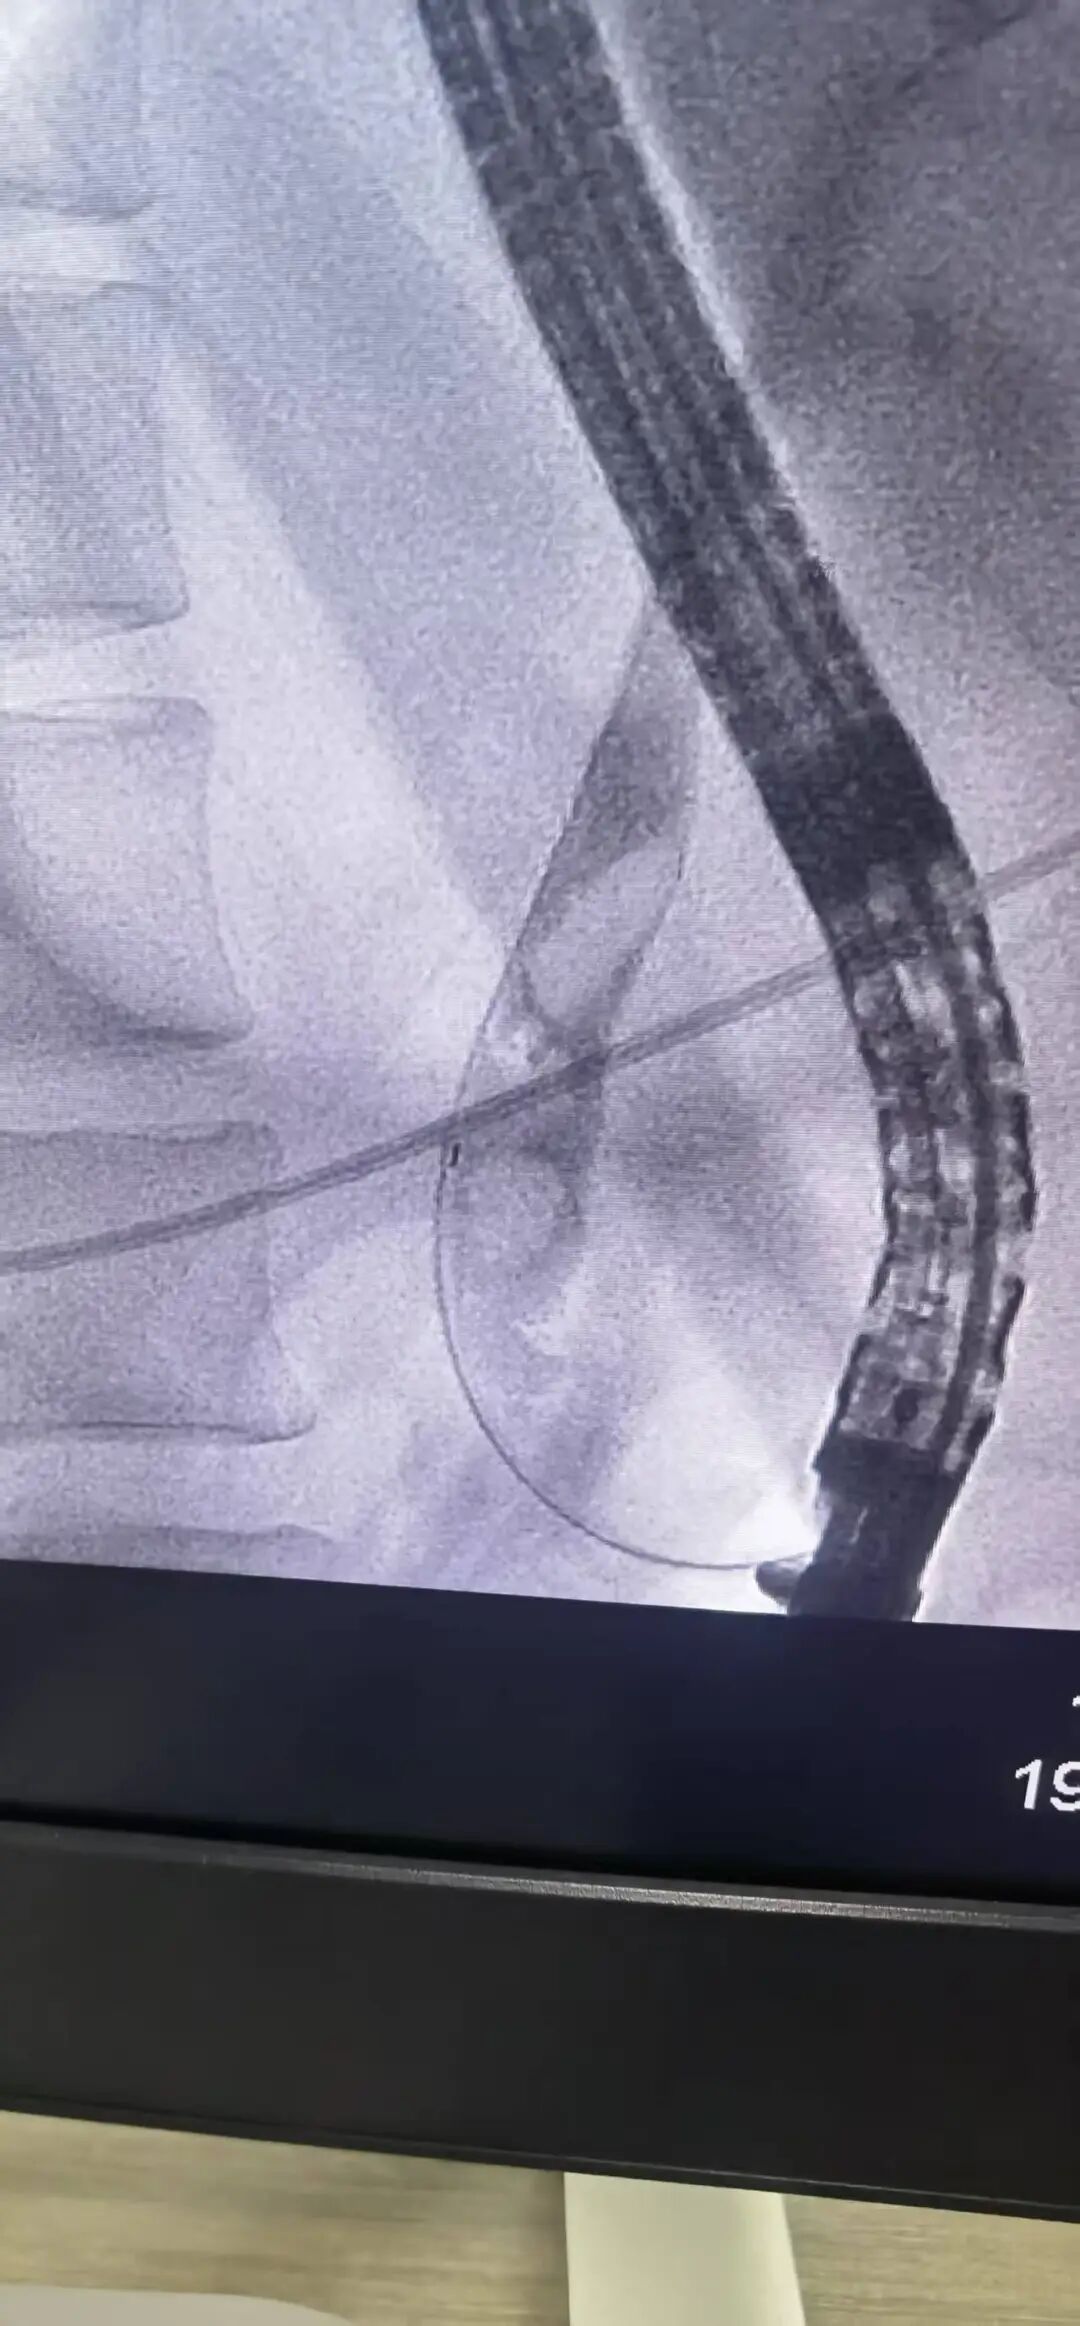

· 精准插管: 在十二指肠镜视野下,专家手法娴熟,一次性成功选择性胆管深插管,为后续操作奠定了坚实基础。

· 巧妙取石: 造影显示,患者胆总管下端有3颗直径约1.5cm的嵌顿性结石。专家采用球囊扩张、网篮取石等一系列高精尖技术,成功将结石完整取出,瞬间,淤积的胆汁顺利引流通畅。

· 鼻胆管引流: 为充分引流、控制感染,术中顺利放置了鼻胆引流管。整个手术流程如行云流水,仅用时不到半小时的时间便宣告成功。患者生命体征平稳,梗阻即刻解除。